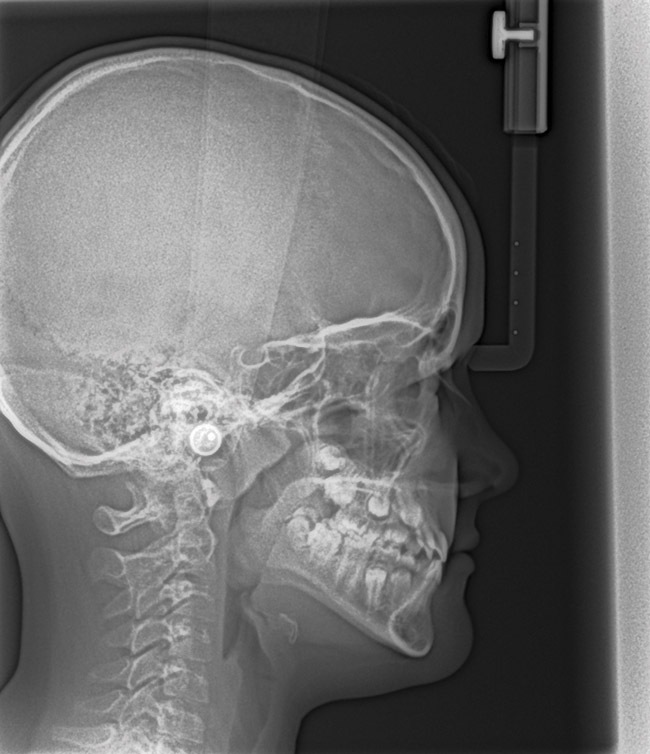

(15.) Cephalometric evaluation demonstrates significant tonsillar blockage of the airway and bimaxillary retursion.

Figure 15